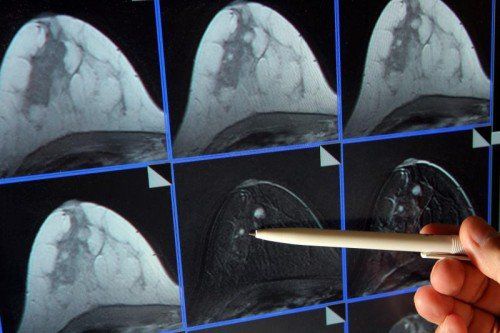

Die Mammografie ist eine wichtige Früherkennungsmaßnahme. Die Einladung dazu erfolgt alle zwei Jahre. DPA